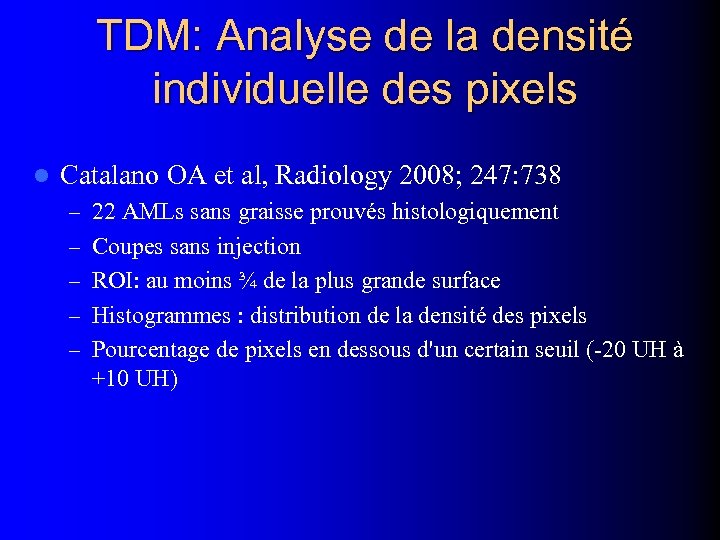

TDM: Analyse de la densité individuelle des pixels l Catalano OA et al, Radiology 2008; 247: 738 – 22 AMLs sans graisse prouvés histologiquement – Coupes sans injection – ROI: au moins ¾ de la plus grande surface – Histogrammes : distribution de la densité des pixels – Pourcentage de pixels en dessous d'un certain seuil (-20 UH à +10 UH)

TDM: Analyse de la densité individuelle des pixels l Catalano OA et al, Radiology 2008; 247: 738 – 22 AMLs sans graisse prouvés histologiquement – Coupes sans injection – ROI: au moins ¾ de la plus grande surface – Histogrammes : distribution de la densité des pixels – Pourcentage de pixels en dessous d'un certain seuil (-20 UH à +10 UH)